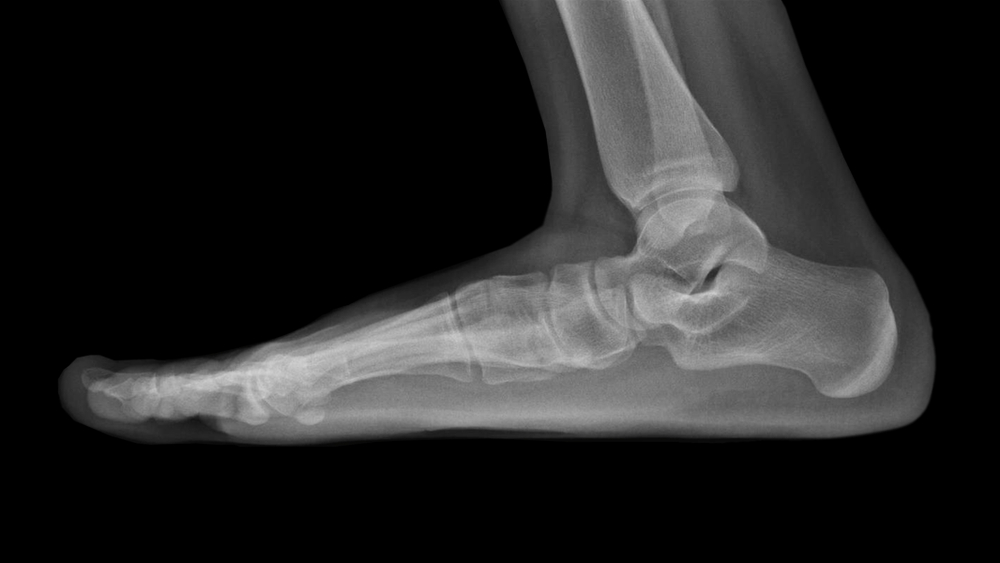

Flat feet, or Pes Planus, are common foot conditions. In a healthy foot, an arch forms on the inner side. When you’re standing, a little space like that is very acceptable. People who suffer from Pes Planus, sometimes known as “Flat feet,” have an arch that is abnormally low or nonexistent. When this arch is absent, the feet have the propensity to roll inward when walking or standing, and they have the propensity to point outward. If you ever find yourself in need of medical attention, Doral Health & Wellness is open around the clock to accommodate you. People go to Podiatrists in Brownsville when they have issues with their feet or ankles. Podiatrists are medical professionals that focus on diagnosing and treating conditions related to the lower extremities. When it comes to treating wounds and performing surgery on the lower extremities, they are unrivaled. If you have diabetes and are having foot pain, seeing a Foot Doctor in Brooklyn may be helpful.

Just 20% of all adults have pes planus. The breakdown of the medial longitudinal arch is to blame. The degree of flexibility or rigidity is variable. A flexible malformation allows the plantar arch to realign itself to its proper position.